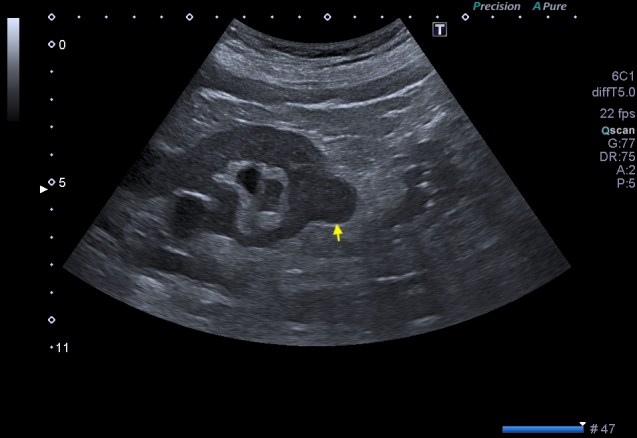

La imagen típica de hepatopatía crónica sería esta:

Puedes observar la superficie hepática en forma de olas y la heteroecogenicidad del hígado..

Compara la dos imágenes y percibe los cambios, así podrás reconocer siempre estos cambios.